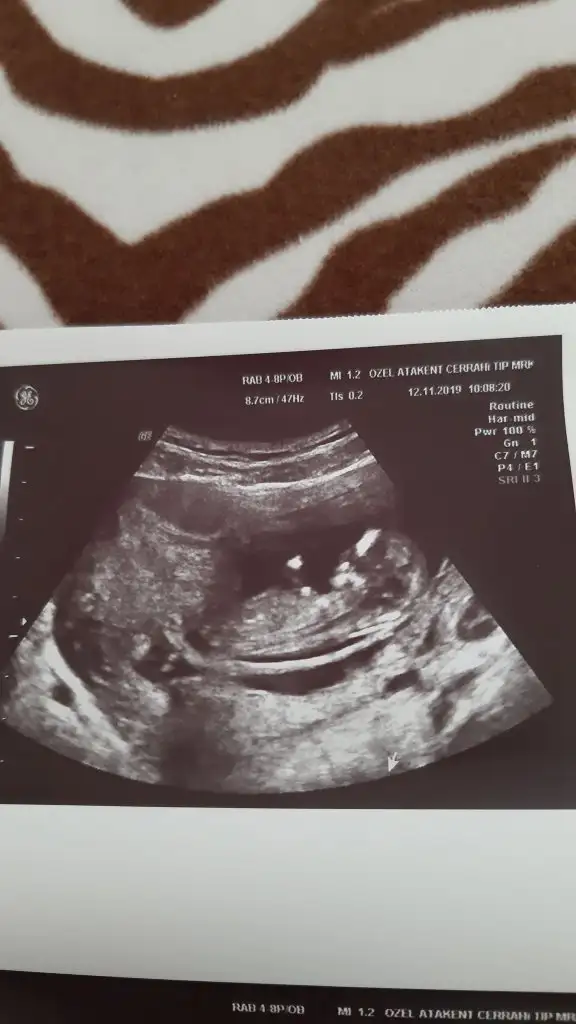

Karındansa kız vajinal ise erkek kaç haftalık burda 11 yada 12 haftada nub tahmini yaparım paylaşırsanızÇok minik ama

Yok 7 haftalık burda ilki vajinaldı o zaman 5 haftalıktı en son bu resimdekiydi perşembe yine gidicem 8+5 olucak o zaman erken ama işte merak ettim :)Karındansa kız vajinal ise erkek kaç haftalık burda 11 yada 12 haftada nub tahmini yaparım paylaşırsanız

Ya rica etsem benim vajinal ultrasona göre 6.hafta ultrasonuma bakabilir misiniz. Bulantım kusmam yok ama halsiz ve iştahsızım5 yada 6 hafta usg varsa paylaşın yada 11 yada 12 hafta oldugunuzda paylaşın nub uygunsa kız yada erkekse tahmin ederim

Erkek olabilirYa rica etsem benim vajinal ultrasona göre 6.hafta ultrasonuma bakabilir misiniz. Bulantım kusmam yok ama halsiz ve iştahsızımEki Görüntüle 2575264

Karşına al usg yi vajinal sağ erkek sol kız senin sağda hayırlı evlat olsunBana da hep erkek gibi geliyor ama vajinal ultrasona göre ters mi çevirmeliyim yani ultrasonla vajinal ultrason sağ sol çatışması yaşıyorum şuan

Canim cin takvimi yap bence cikiyo simdiye kadar kime yaptysam cikti tabi Allah ne derse o olur bide keseye bak kese uzunsa erkek yuvarlaksa kiz8 haftalık hamileyim ama cinsiyetini çok merak ediyorum sürekli mide bulantım var hiçbirşey yemek istemiyorum özellikle tatlı hiç yemiyorum tuzlu yiyorum çubuk kraker tarzı sıkça elma yiyorum ve bel ağrım çok oluyor halsizlikde fazlasıyla yardımcı olabilir misiniz ki acaba